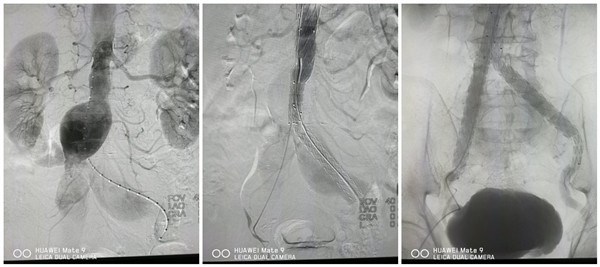

患者韩某、男性、以“发现高血压5年,头晕10天”之主诉入院。入院后积极完善相关检查,CTA结果示:腹主动脉、双髂总动脉动脉瘤,伴附壁血栓。左颈总动脉,锁骨下动脉夹层。根据患者具体情况,主管医生马建仓副主任医师、李宗禹主治医师、关昊住院医师为该患者实施了“腹主动脉、双侧髂动脉动脉瘤腔内隔绝术”,经右侧股动脉血管鞘置入金标猪尾,行腹主及髂动脉造影,显示肾动脉平面下约2cm腹主动脉瘤起始,瘤颈直径约21mm,腹主动脉瘤最大直径6cm,瘤颈至双髂动脉起始端长度约90mm,双侧髂动脉动脉瘤形成,直径分别32mm、38mm,双侧髂内动脉未见显影。手术过程顺利,出血少、创伤小,在术后第二天,患者已经顺利出院。

以往治疗腹主动脉瘤的手术方法为:由腹部中央切开30cm切口入腹。切开瘤体、用人造血管植入代替病变血管,重建腹主动脉的连续性。血管内支架治疗手术的发展使得腹主动脉瘤的治疗可以避免既痛苦且较危险的正中开腹手术,这项手术是血管内手术的一种,其所有的治疗都经伸入动脉血管内的导丝、导管、支架等治疗器材,在X线血管造影的导引下完成,因此血管不需要实际的剥离或缝合,所以有伤口小、失血少、疼痛轻、恢复快等低侵袭性的优点。

普通外科为该患者实施的“腹主动脉、双侧髂动脉动脉瘤腔内隔绝术”,是用血管内支架来治疗腹主动脉瘤,相对于传统手术而言有许多的好处。首先是开刀伤口为两侧大腿的小伤口,而不是需要实行30公分的开腹伤口,当然手术之后的恢复时间明显缩短,短期内就可以出院。其次,手术失血量、手术心肺并发症以及手术相关死亡率也都明显下降。使用血管内支架治疗,由于不需要把主动脉整个夹住,病人的血流力学改变不大,对于心肺系统的压力较小,所以术后心肺功能的恢复快,同时由于整个手术的进行都在腔内完成,对于身体其他部位的影响也减到最低,所以手术的危险也降低到开腹手术的三分之一。普通外科目前已成功开展此类手术,治疗效果满意,病人恢复很快,术后并发症明显低于传统手术方法。随着学科的不断发展和进步,普外科血管外科手术例数逐年增长,现在已经能够娴熟的完成周围血管各类介入手术治疗,帮助兄弟科室解决困难,为了患者的康复共同努力。